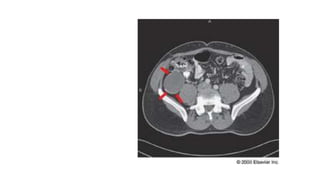

• Apendicitis aguda

• Rx simple: niveles hidroaeros localizados al ciego o colon ascendente, signo

de colon interrumpido ileo, gas en colon transverso, escoliosis de concavidad

derecha, desaparición de la línea del psoas derecho, apendicolito

• US: evaluar si esta perforada, elección para embarazadas

• TC: para obesos

• Apendicitis aguda •Rx simple: niveles hidroaeros localizados al ciego o colon ascendente, signo de colon interrumpido ileo, gas en colon transverso, escoliosis de concavidad derecha, desaparición de la línea del psoas derecho, apendicolito • US: evaluar si esta perforada, elección para embarazadas • TC: para obesos